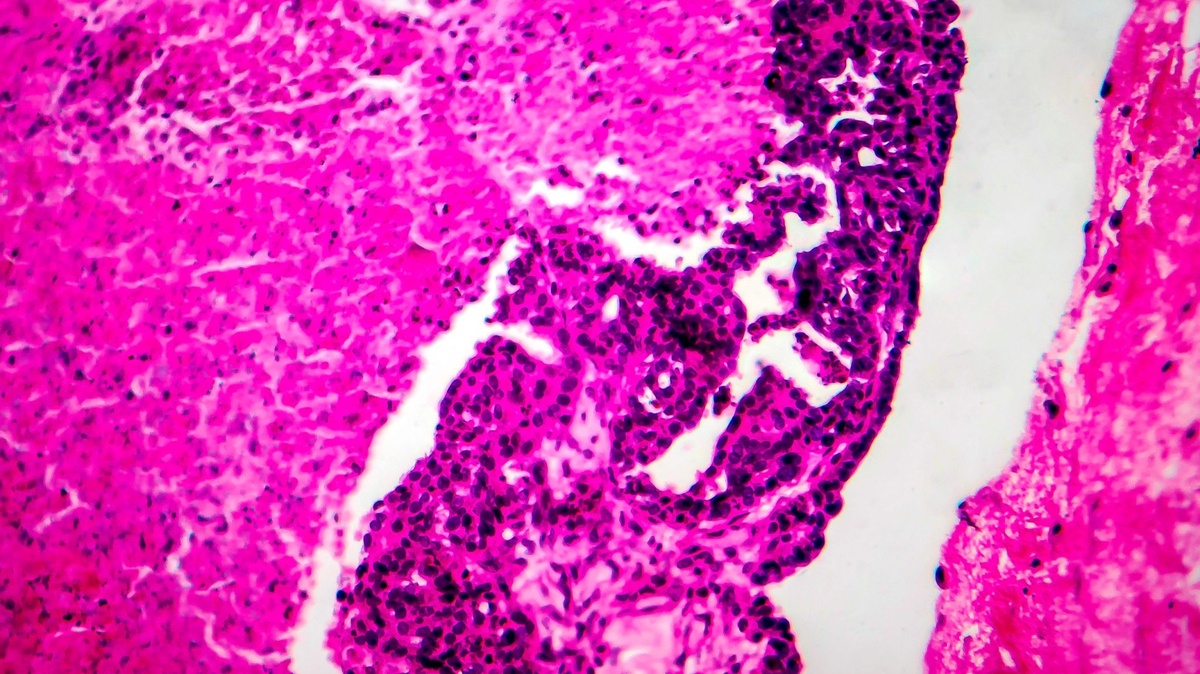

Некоторым пациенткам с серозной карциномой яичников, которые перенесли радикальную резекцию, можно отказаться от проведения химиотерапии и ограничиться эндокринотерапией летрозолом. Такое лечение связано с более низкой частотой тяжелых побочных эффектов.